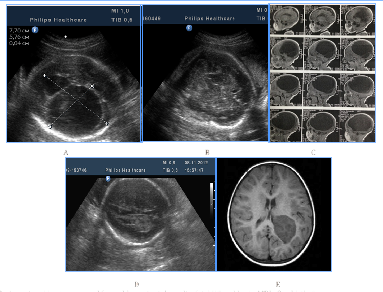

To distress associated antenatal US features of fetal brain could include signs of cortical dysplasia, antenatal intraventricular hemorrhage and PVL (Figure 9) (Figure 10). PVL in the form of small cyst was observed in two fetuses with different premorbid background one fetus with severe prenatal distress and the others with neuroinfection. Particularly attention deserved severe postnatal aftermath of fuzziness and reduced contrast of the fetal brain structures due to cerebral edema and cortical laminar necrosis at 5cases which had different pathogenetic background (Figure 10). Such contrast of structures looked like a result of wrong exposure while getting a picture, but thats were real images, with progression of edema structures looked absolutely "blurred" and cystic PVL lesions were detected. Postnatal catamnesis of all cases was extremely unfavorable.

Figure 9Antenatal distress associated sonographic brain features.

Figure 10Fetal distress associated small-cystic PVL in the fetus and newborn.

A number of fetal intracranial changes as cortical dysplasia, intraventricular hemorrhage, PVL and reduced contrast of the fetal brain structures were observed both in infection and in severe placental dysfunction. Most of such anomalies had periventricular or subependymal localization, which could associated with universal polyetiologic pathogenetic mechanism of the germinal matrix injury. Figure 9 Antenatal distress associated sonographic brain features. A) Revers diastolic flow in the umbilical artery. B). fuzziness and reduced contrast of the fetal brain structures due to cerebral edema on the background of antenatal distress and metabolic acidosis. In clinical catamnesis perinatal loss and extremely severe persistent neurologic morbidity.

Figure 10 Fetal distress associated small-cystic PVL in the fetus and newborn. A) 31 GW, severe IGR, fetal metabolic acidosis, fuzziness and reduced contrast of the brain structures due to cerebral edema, skull deformation due to cortical necrosis, small cysts PVL in the intermediate zone (arrow). B) NSG of the newborn's brain of on the 2nd day of life, progressive small-cystic PVL. Neonatal death.